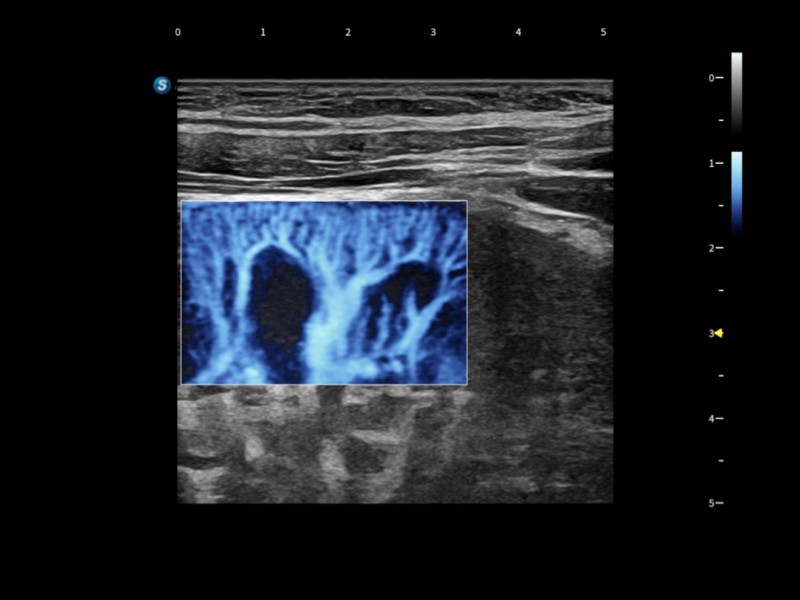

在传统血流的基础上优化扫查和算法策略,能够更好的抑制组织信息,提炼红细胞运动信息,得到更高帧频,高灵敏度和分辨率的血流信号,还原更真实的血流动力学。

通过光照模型,使二维血流显示出立体的效果,增加血流的敏感性、成束性,减少外溢。可以和其他不同的血流技术联合使用,融合不同技术的优势。轻松应对微小血管,增强血流的立体效果,提升视觉敏感性。

通过创新的Matrix E自适应滤波算法,能有效滤除软组织和噪声信号,最大限度保留超低速微细血流的信号;结合超长时间域算法,极大提升细微血流的敏感性和空间分辨率,更真实的反应组织、包块的血流灌注情况。